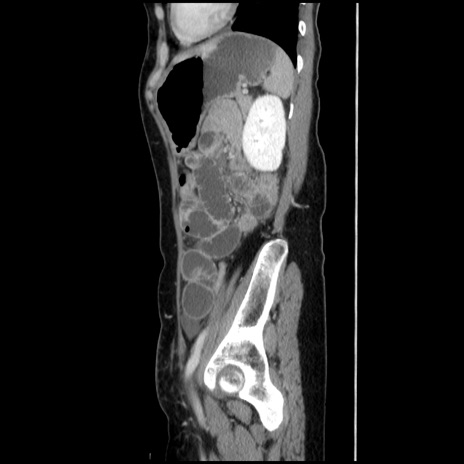

横断像

【症例】40歳代 女性

【主訴】上腹部痛、嘔気・嘔吐

【現病歴】約9時間前頃から急に上腹部痛、嘔気、嘔吐が出現。改善しないため救急要請。

【既往歴】子宮頚癌(広汎子宮全摘術、放射線療法)、腸閉塞

【身体所見】腹部:平坦、軟、腸雑音亢進、上腹部を中心に腹部全体に圧痛あり。

【データ】WBC 8400、CRP 0.03